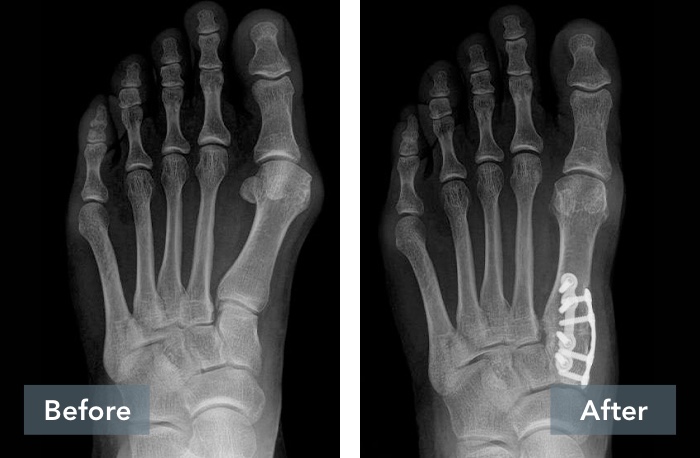

See the Results

Lapiplasty® Before & After Results

A common misconception is that a bunion is simply a “bump” that can be “shaved off.” But, bunions are more than a bump – they are complex 3D problems caused by an unstable joint in the middle of the foot. While the majority of bunion surgery is only 2D and fails to address the root cause, Lapiplasty® provides a 3D correction and secures the unstable joint.

While traditional 2D osteotomy surgery merely cuts & shifts the bone to address the cosmetic bump, Lapiplasty® 3D Bunion Correction™ does more — it corrects the entire bone in 3D and secures the unstable foundation to get you back on your feet quickly in a walking boot. The Lapiplasty® Procedure has also shown low recurrence; 97% and 99% maintain 3D correction in 13 and 17 months respectively.1,3